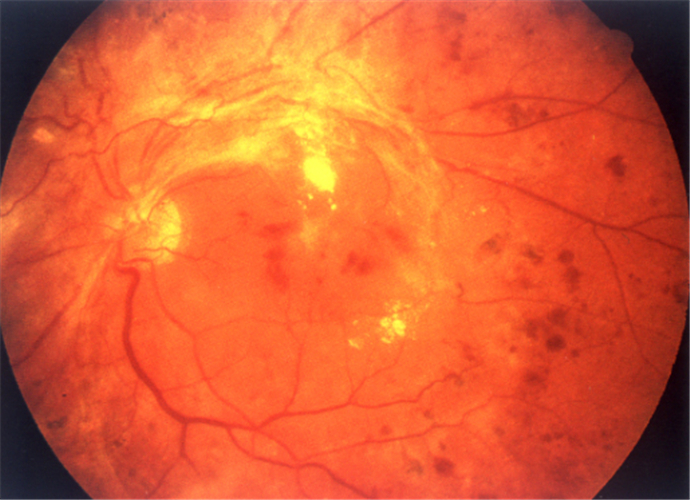

增生引起視網膜脫落

增生併發視網膜脫落